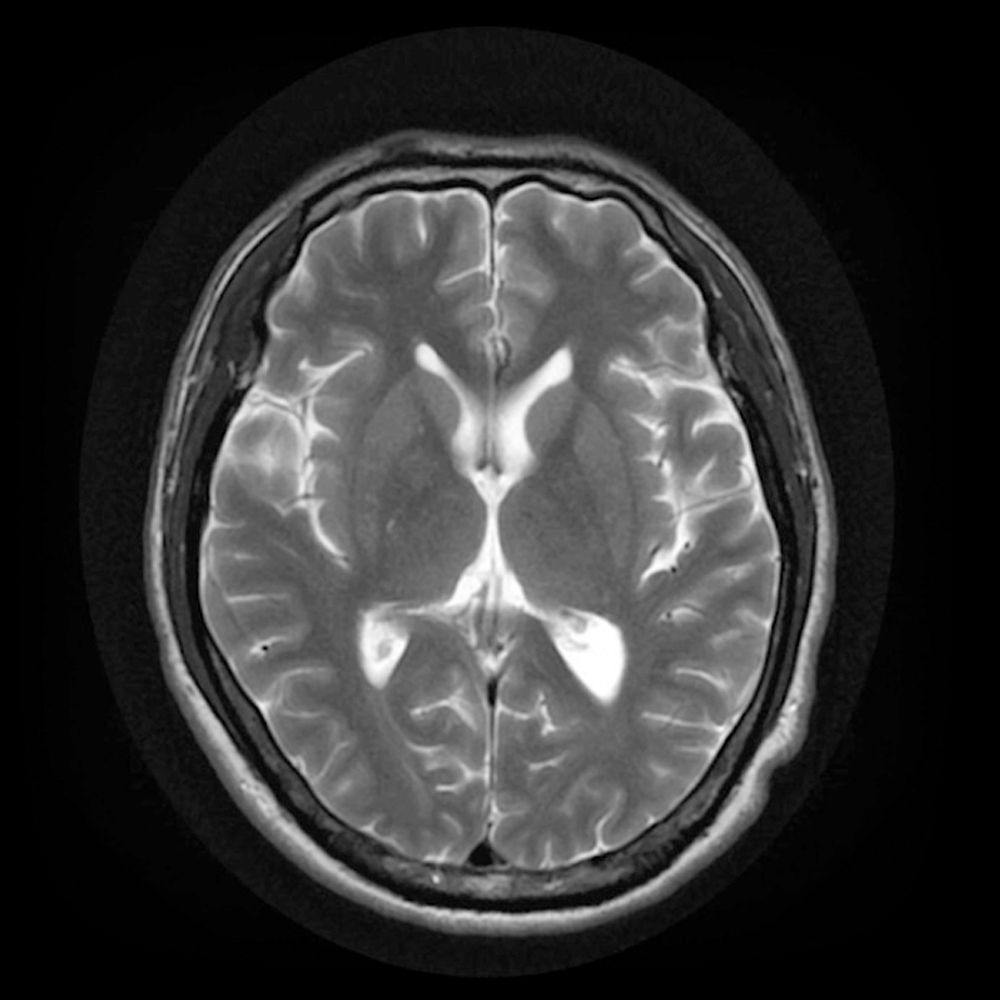

AI-MRI 是一套結合 邊緣/雲端運算技術 與 醫療影像 AI 分析的腦部 MRI 智慧判讀系統,針對神經相關疾病(如中風、腦瘤、AVM)提供結構性與多階段的診斷支援,有效提升臨床效率與判讀準確率。

AI-AVM 是一款部署於雲端的智慧醫療軟體,專為腦部動靜脈畸形(AVM)病患設計,結合 T2 加權 MRI 影像 與 TOF(Time-of-Flight)磁振血管造影,能夠自動完成病灶輪廓描繪、組織分割與手術風險初步分級等影 像分析任務,協助放射科、神經外科及腫瘤治療團隊在規劃放射治療時,快速掌握病灶特徵與空間分布。

透過深度學習神經網路,AI-AVM 對病灶血管(Nidus)、正常腦組織與腦髓液(CSF)進行精準分割,並計 算體積與組織比例等統計數據,為後續治療計畫提供客觀依據。系統亦支援 Spetzler-Martin 分級評估,根據 影像特徵給出 AVM 大小評分,並讓醫師依臨床狀況補充位置與靜脈灌流資訊,以完成分級。所有分析結果以 可視化呈現,並可匯出 DICOM RTSS 結構集,便於後續規劃與團隊溝通。

透過匯入 MRI T2 與 TOF 影像,系統能自動完成影像對齊與疊加處理,減少醫師在不同影像序列間切換的時間負擔。同時,我們的 AI 模型會自動標記出疑似病灶位置,並清楚區分:紅色:病灶血管 (Nidus)、綠色:正常腦組織、藍色:腦髓液 (CSF)